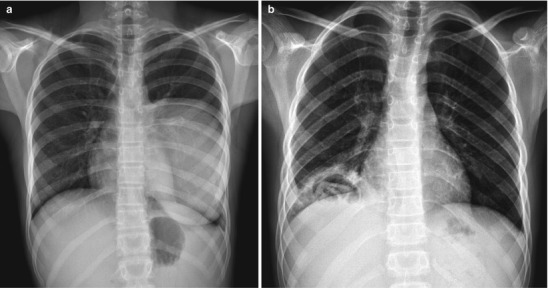

Pulmonary dissemination, usually seen in very young and immunocompromised patients, leads to the formation of pulmonary nodular interstitial granulomas, usually 1–2 mm in size, throughout the lungs. Chest radiographs demonstrate the usual miliary nodular pattern but CT is more sensitive for the detection of miliary TB (Kim et al. 1997) (Fig. 13.21). Adult-type disease presentation is common after primary infection in children over 10 years of age or via endogenous reactivation (postprimary TB) or reinfection. Chest radiograph shows ill-defined, fibronodular parenchymal disease and cavitation mainly involving the apical segments of the upper lobes (Perez-Velez and Marais 2012) (Fig. 13.22).

Fig. 13.22.

Reactivation TB. Chest radiograph of a 13-year-old boy with chronic cough and shortness of breath showing fibrotic changes, pleural thickening, and volume loss in the right lung